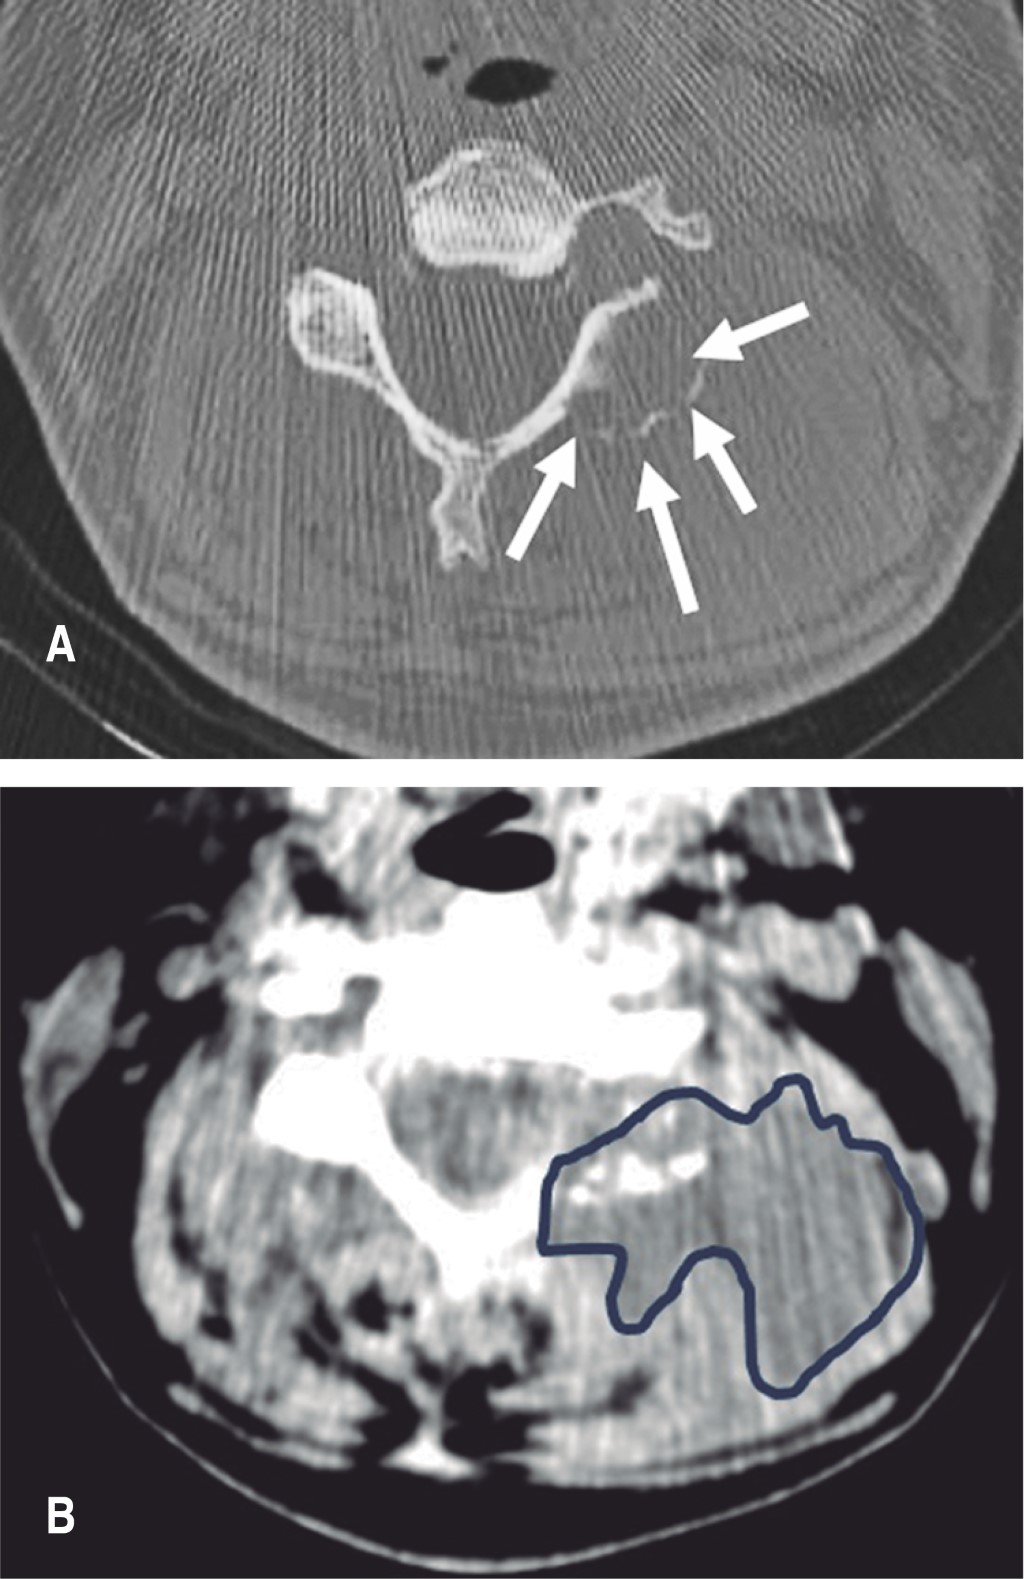

A la consulta al cirujano espinal, por la persistencia de cervicalgia (9/10) a pesar del reposo e inmovilización con collar, se observa en la tomografía computada la afectación de articulación facetaria C4-C5 izquierda con compromiso de partes blandas (Figura 1).

Se realiza toilette quirúrgica con fijación C3-C5 con tornillos facetarios y barras (Figura 3). El cultivo de colección y partes blandas dio positivo a Staphylococcus aureus meticilino sensible y el estudio de anatomía patológica la afectación ósea aguda. Continuó con vancomicina por seis meses con indicación de infectología, con buena evolución local.